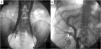

Cavography through bilateral femoral access, showing the completely duplicated inferior vena cava (IVC) (A) with bilateral azygos continuation and no retrohepatic segment. There were 3 branches of the right IVC (B). The 2 lateral branches crossed the liver and drained the right hepatic vein. The medial branch continued under the right pillars of the diaphragm, as the right azygos vein.